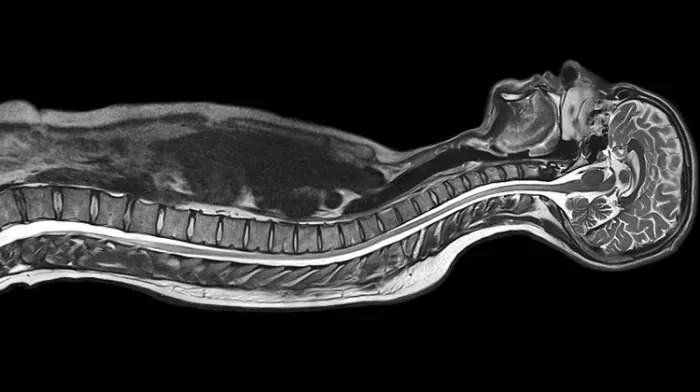

Slika tela i organa koju daje magnetna rezonanca MRI

Ono što magnetnu rezonancu čini nezamenljivim dijagnostičkim alatom je činjenica da je ljudski organizam većinom sačinjen od vode. Kada se pacijent izloži radiofrekventnim talasima, protoni u atomima vodonika, kojih je u ljudskom organizmu izuzetno mnogo, a koji su pobuđeni jakim magnetnim poljem, odašilju povratni radiofrekventni signal. Ovaj signal je posledica fenomena rezonancije, po kom je metod i dobio ime. Mašina snima ovaj signal i na osnovu njega pravi sliku unutrašnjosti tela. Analizom snimaka lekar je može da razlikuje benigno od malignog mekog tkiva.